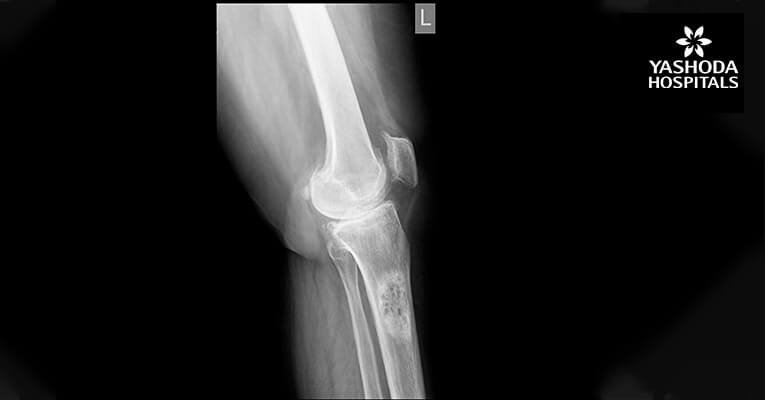

Preop X-Ray

Post-op X-Ray